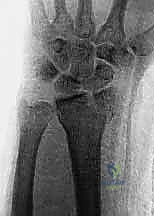

- الكعبرة البعيدة (Distal Radius): هي النهاية السفلية لعظمة الكعبرة (العظمة الأكبر في الساعد من جهة الإبهام). تشكل هذه العظمة الجزء الأكبر والأهم من مفصل الرسغ، وتتحمل حوالي 80% من القوة المنتقلة من اليد إلى الساعد.

أي كسر في هذه العظام، خاصة إذا امتد إلى داخل السطح المفصلي (Intra-articular fracture)، سيؤدي إلى اختلال الميكانيكا الحيوية للرسغ بأكمله. إذا لم يتم تسوية السطح المفصلي بدقة متناهية (بحيث لا يتجاوز الفارق 1 مليمتر)، فإن الغضروف سيتآكل بسرعة، مما يؤدي إلى ألم مزمن وخشونة مبكرة.

الأعراض والعلامات التحذيرية: متى يجب التدخل الفوري؟

إذا تعرضت لسقوط أو إصابة في يدك، فهناك علامات واضحة تدل على احتمال وجود كسر في الكعبرة البعيدة أو الزند الإبري. تجاهل هذه الأعراض قد يؤدي إلى التحام العظم بشكل خاطئ (Malunion)، مما يتطلب جراحات تصحيحية معقدة لاحقاً.

- تشوه شكلي واضح: في كسور كوليس، قد يأخذ الرسغ شكل "شوكة العشاء" (Dinner Fork Deformity) بسبب انزياح العظم.

يتم تحديد خطة العلاج من قبل الأستاذ الدكتور محمد هطيف بناءً على تقييم دقيق للصور الشعاعية (X-ray) والأشعة المقطعية (CT scan) لمعرفة مدى تفتت الكسر وتأثر السطح المفصلي.